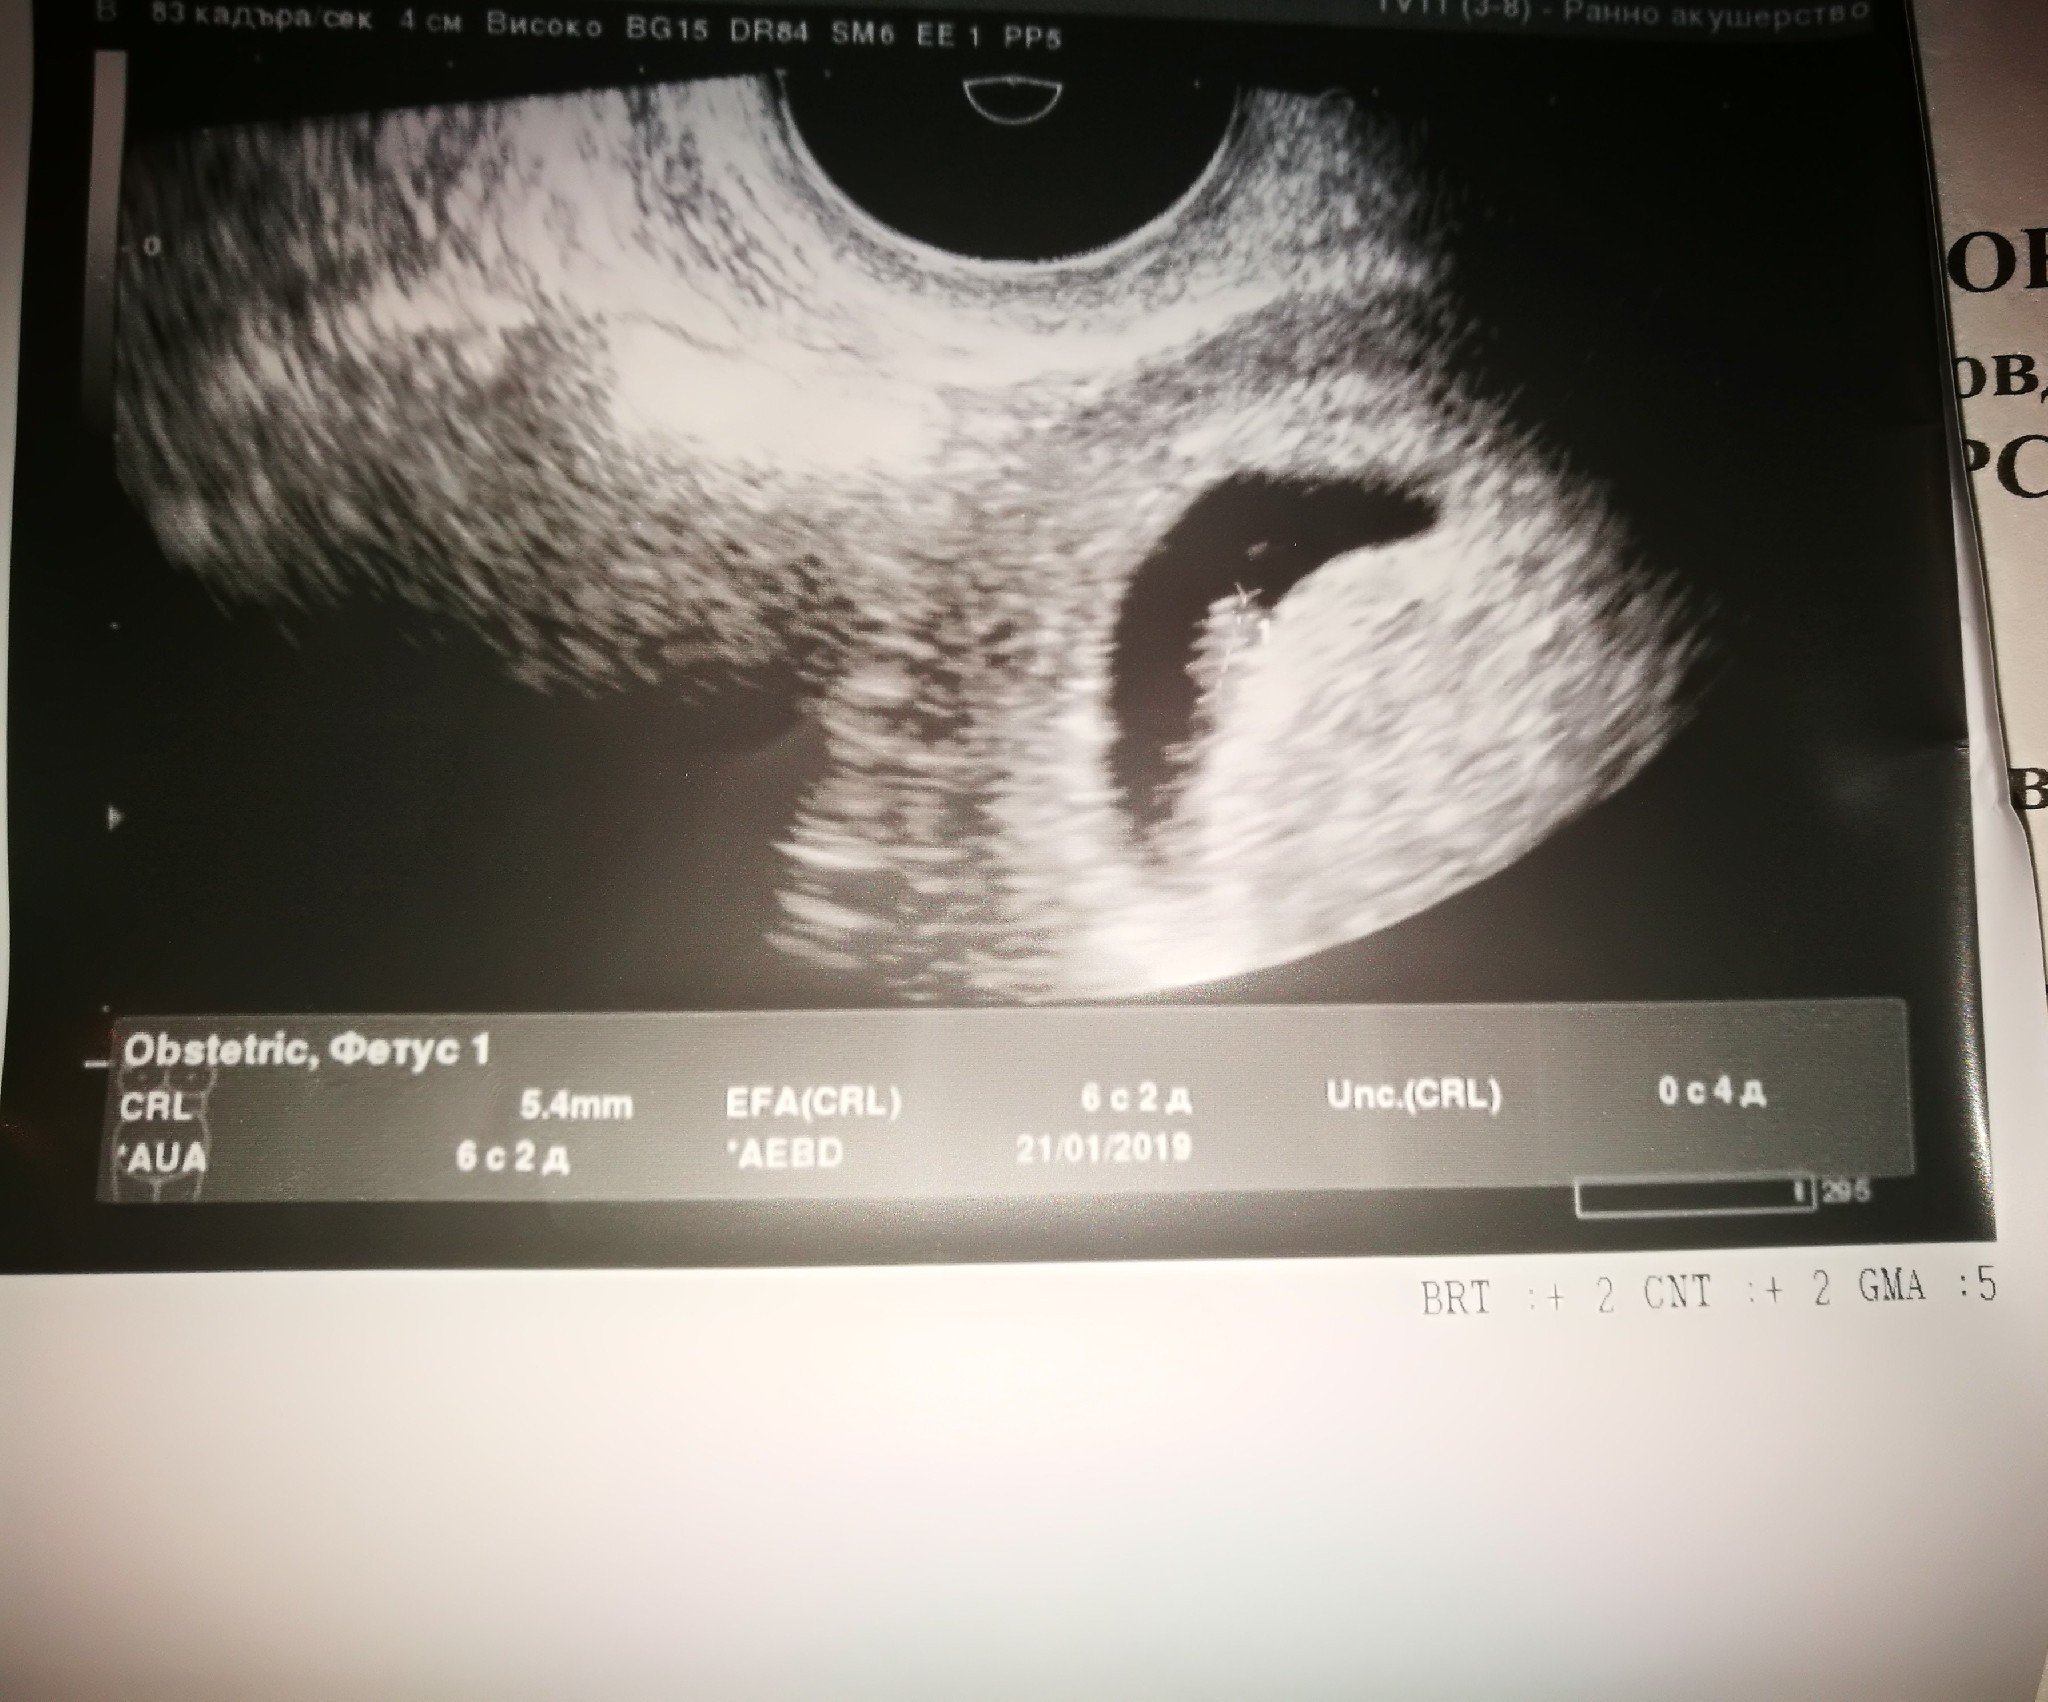

Здравейте пиша отново, днес-видя се бебо и пулсиращо сърце, но ме притесни плодният сак...каква е тази форма...или съм адска параноя

Спокойно, плодния сак си е наред. Формата, която ще излзе на снимката зависи от ехографа как е позициониран и каква част успява да хване.

Точно така. А вагиналната сонда обикновено такива капковидни ги вади изображенията.

Лекарят ти не е намерил нищо обезпокоително, но ти реши да потърсиш компетентно мнение във форума относно тълкуване на ехографско изображение? Понякога просто се изумявам какви ги мъдрите...